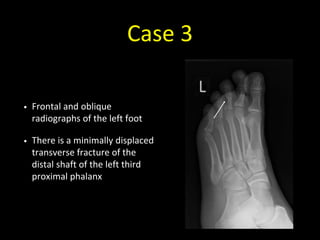

Case 3

• Frontal and oblique

radiographs of the left foot

• There is a minimally displaced

transverse fracture of the

distal shaft of the left third

proximal phalanx

• Note how difficult it is to see

the fracture on the frontal

projection (it’s just about

visible as a transverse dense

line)

• This is why we need two

views when assessing for

fractures

• In this case the projections

are frontal and oblique - the

projections aren’t necessarily

always at right angles to each

other